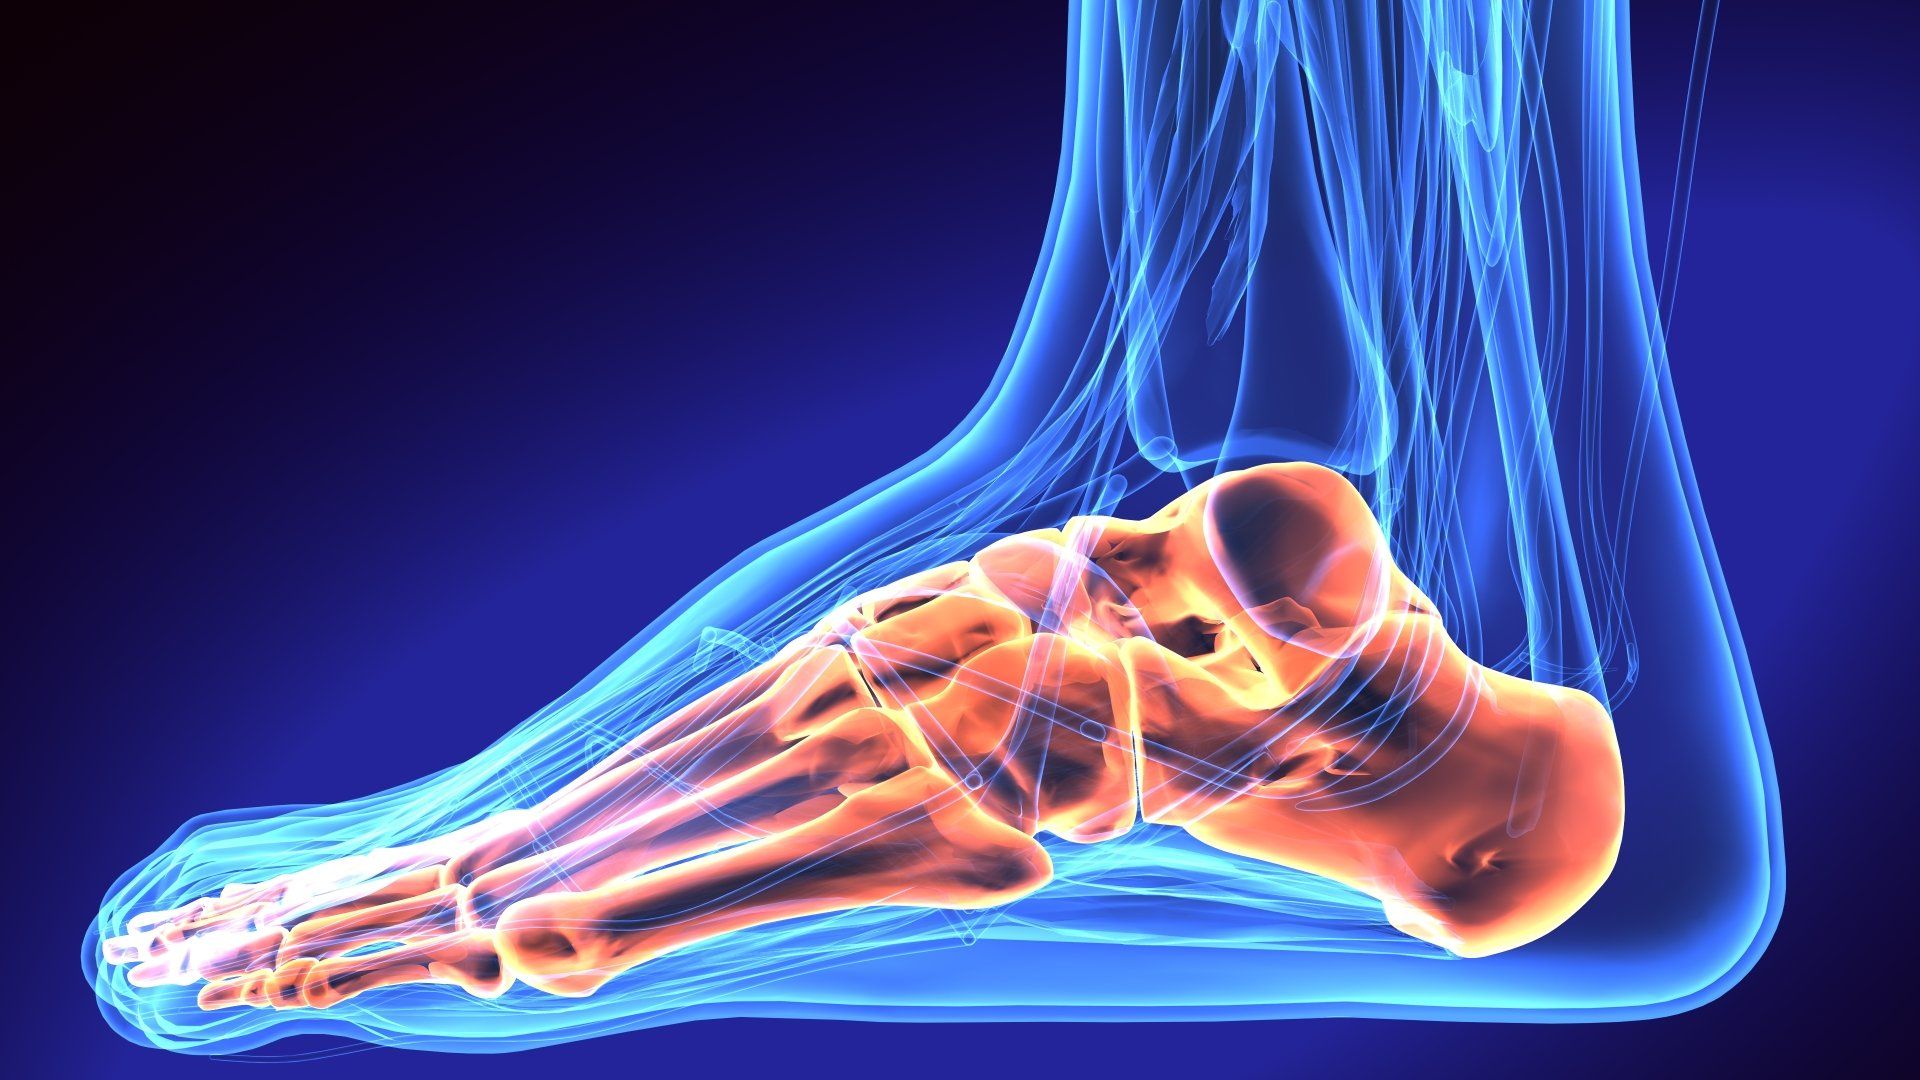

The Achilles tendon is the largest tendon in the body and connects the calf muscle to the heel of the foot. The Achilles is responsible for push off of the ankle with activities. Achilles tendon ruptures typically occurs when a strong contracture of the muscle excessively loads the tendon - resulting in a tear. Most of these injuries occur during sports, and patients often describe the sensation as something struck the back of their leg. A “pop” is frequently felt when the tendon ruptures. Symptoms include swelling, weakness of the leg, palpable defect in the back of the leg and difficulty with walking.